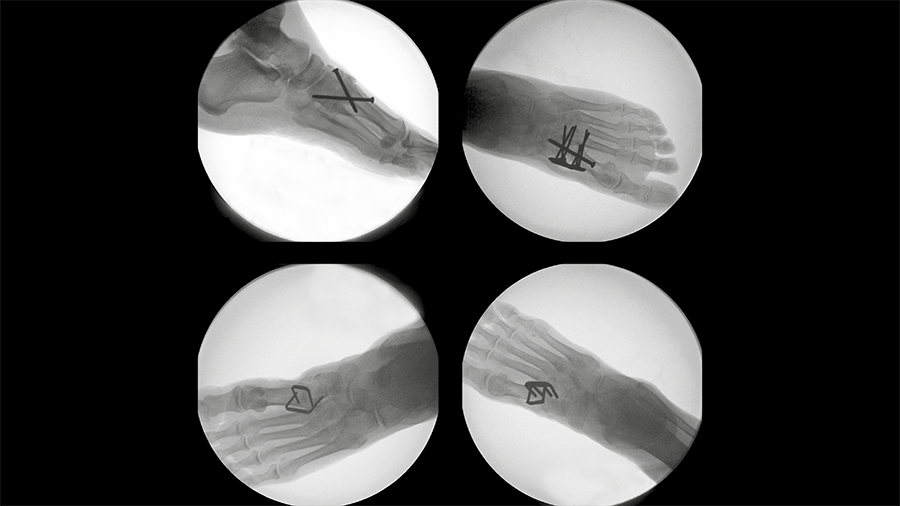

Tarsometatarsal joint fusion

Nitinol stables might demonstrate comparable performance to established techniques for fusion of the first TMT joint.